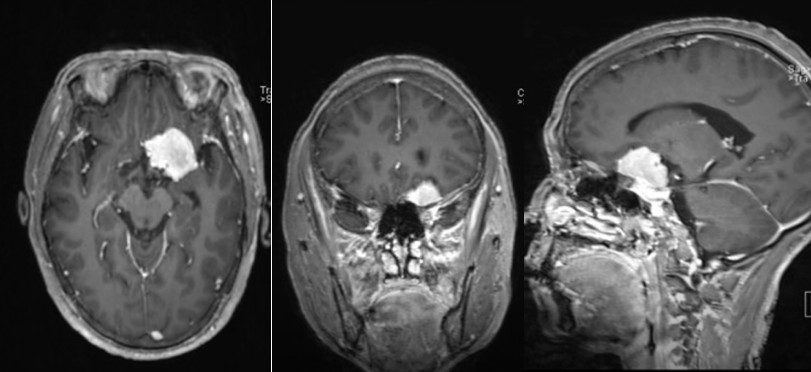

选手们用8分钟的时间分享了手术视频,展示如何利用高速磨钻、Sonopet超声外科吸引系统等打造手术入路、实现脑膜瘤的高效切除,展现了卓越的手术技巧。

(摘自兰州大学第二医院李峤医生分享的案例)